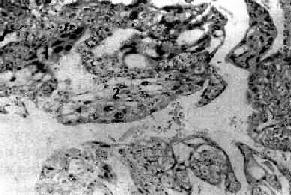

图13-11 葡萄胎

绒毛肿大,间质水肿,血管消失,滋养层上皮增生(图右侧)